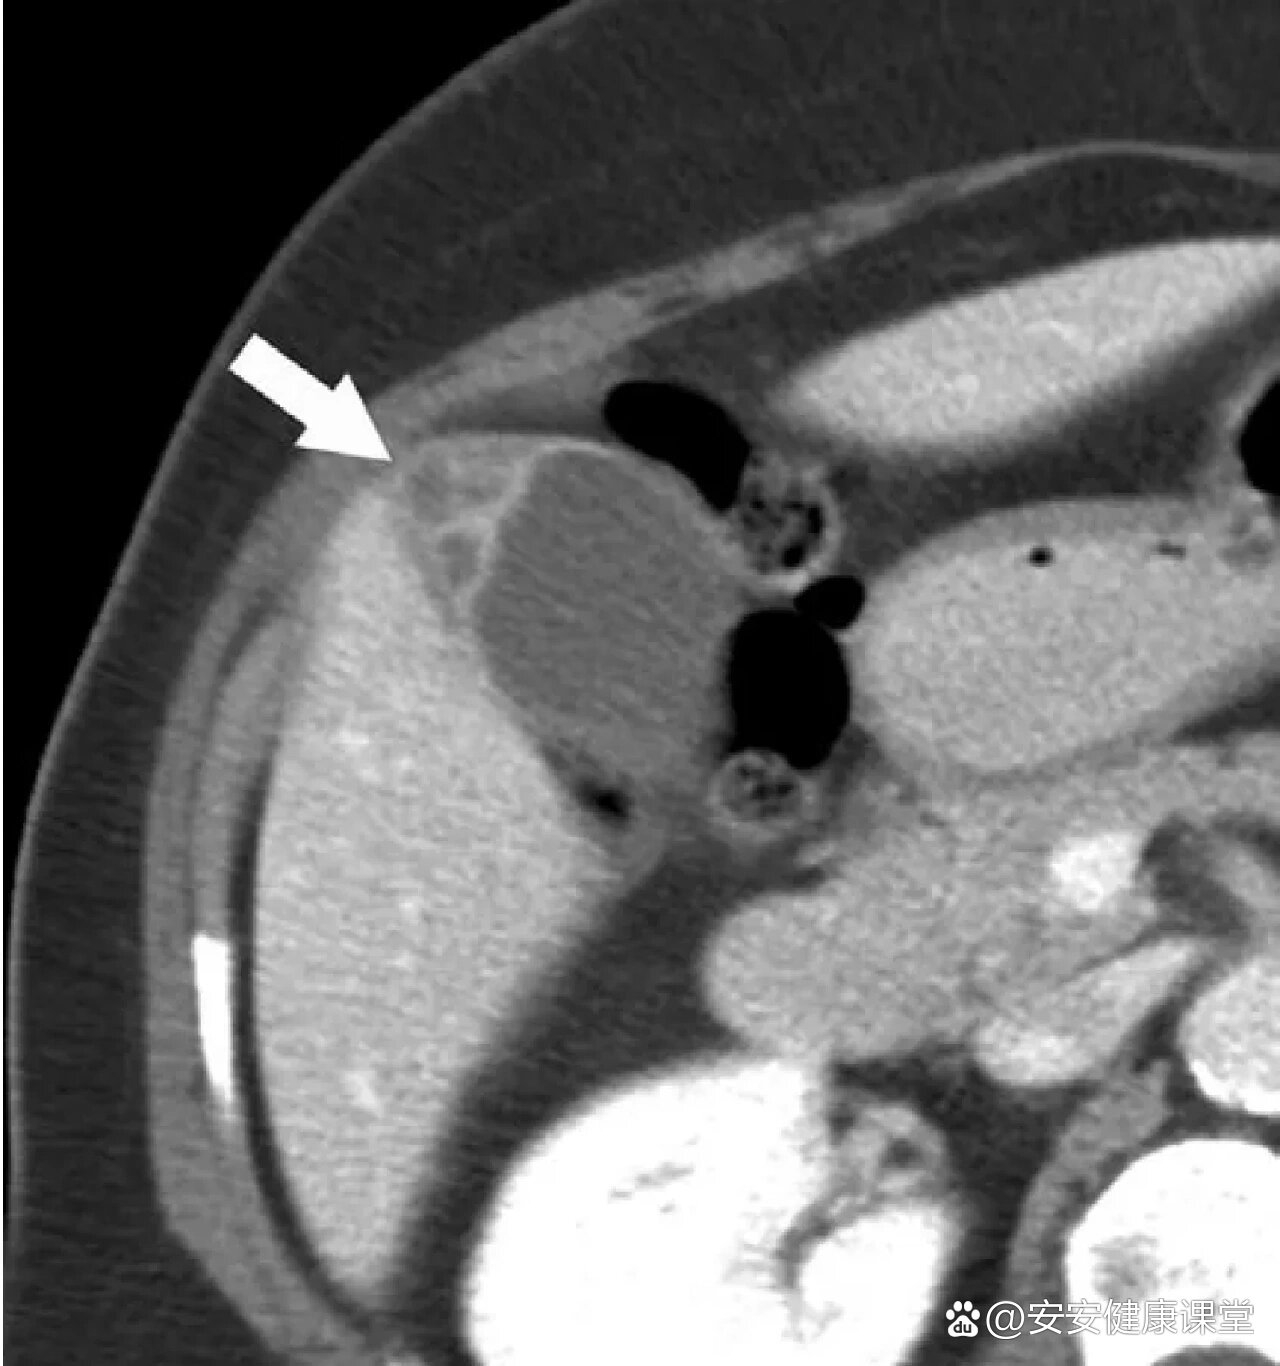

胆囊腺肌症影像表现及鉴别